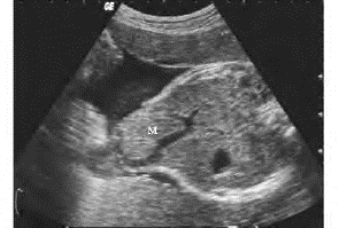

1.22.3三、胎儿先天性心脏病

1.22.4四、体外心、胎儿心脏肿瘤